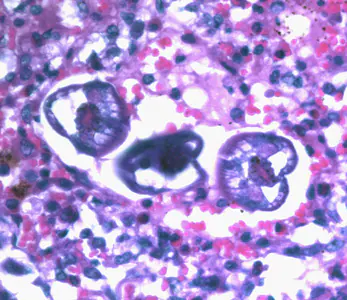

A. lumbricoides in tissue specimens.